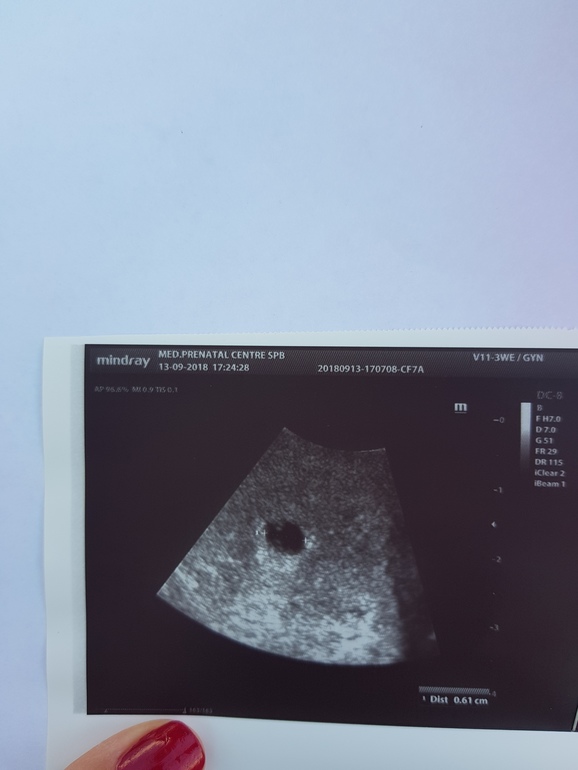

Я разглядела два белых пятнышка и желточный мешочек и скорее всего эмбриончик. Если у вас цикл не регулярный, в сроке вы не уверены, нужно смотреть динамику через недельку, уже наверное сердечко застучит.

Видно пятнышко внутри! Яйцо точно не пустое,скоро там будет малыш,точнее он уже там есть,просто очень маленький,его не видно)))))) вот моя писчинка!) сейчас ручками-ножками в разные стороны дергает)))) прдождите недельку и появится креветочка!)

Виден желточный мешочек. Значит и эмбрион скоро будет!

Это желточный мешочек пока)) но если есть мешочек - значит есть эмбриончик) через недельку увидите